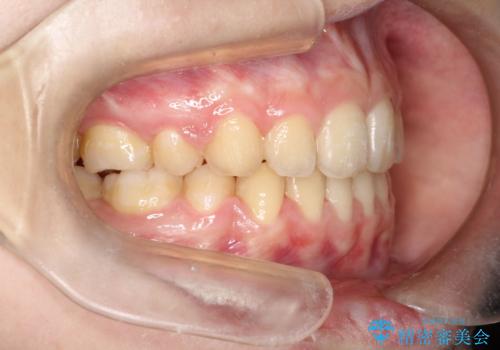

- 口元が出てるのが気になるとのことで来院されました。

歯のがたつきはあまりなかったのですが、口唇が閉じずらく、口元の突出感が確認できました。

上下左右の歯を1本ずつ抜歯して、そのスペースを利用して口元を引っ込める計画としました。